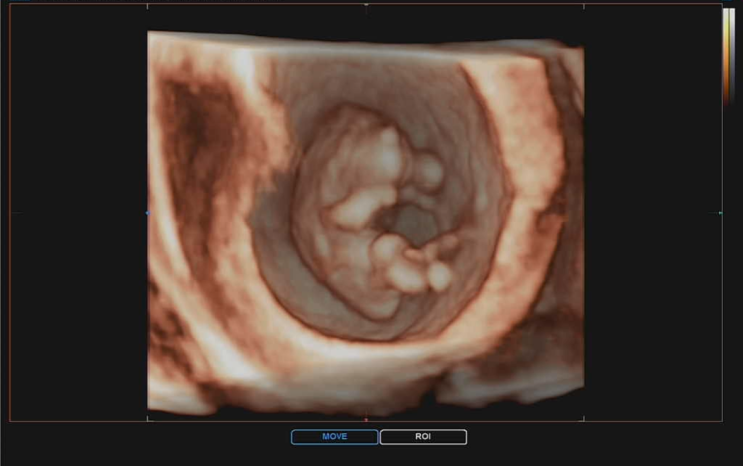

12주 4일 : 1차 기형아 검사, 목투명대 검사, 각도법(이건 누가봐도...?), 입체초음파, 심장소리

임신 중기 임산부 주요 검진 내용 및 주수 10주 이후 : 니프티 검사 가능(고위험 산모의 경우) 12주 : 1차 ...

10주 0일 : 복부 초음파, 젤리곰 시기, 임신초기 입체초음파, 10주차 태아 심장소리

어느 새 10주차 임산부가 되었어요. 그동안 질 초음파로 아가를 확인했지만 드디어 복부 초음파로 아가를 ...